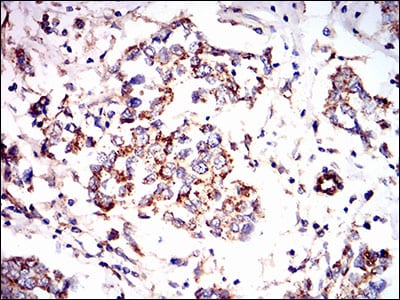

分类: 科研抗体货号: 30598别名: AMPKG应用: IHC,IF,FCM反应种属: Human